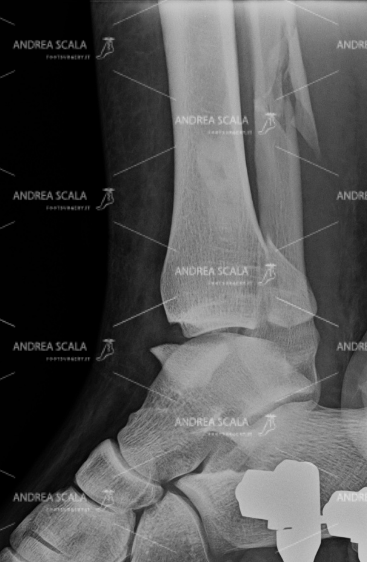

La RXgrafia anteriore mostra che la frattura tri-malleolare è stata operata con impianto di placca e viti. Il risultato post-operatorio è buono e l’articolazione sembra ben ricostruita.

La RXgrafia laterale mostra che la frattura tri-malleolare è stata operata. Il perone è stato ricomposto con placca e viti. Il malleolo tibiale ed il terzo malleolo sono stati ricomposti con viti.